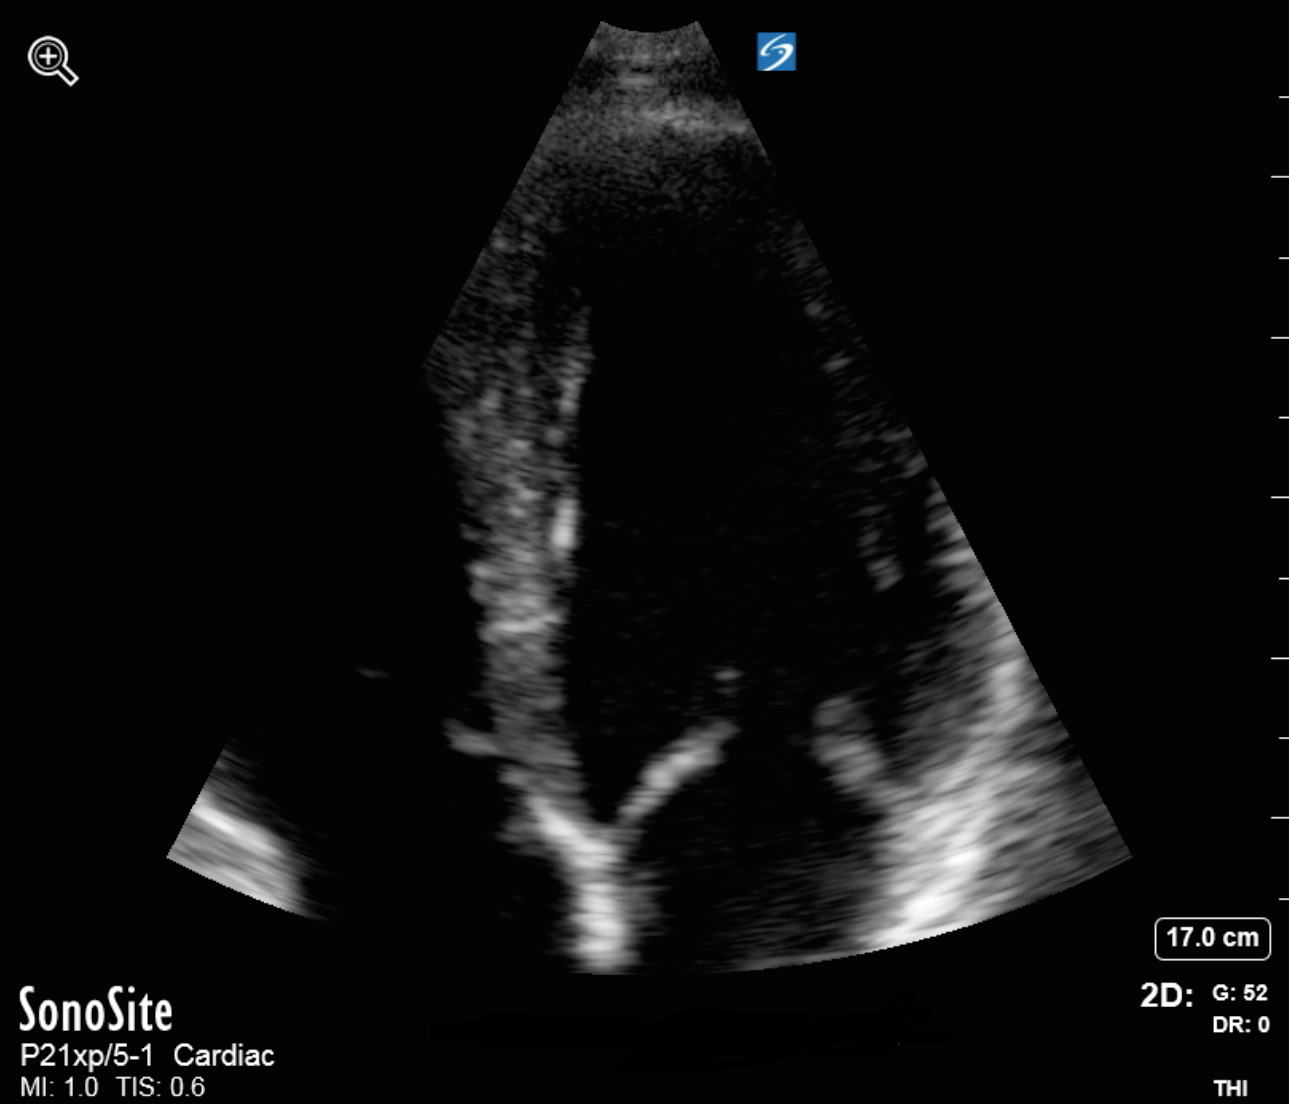

Bild: Mitralklappe, apikal, vergrößert